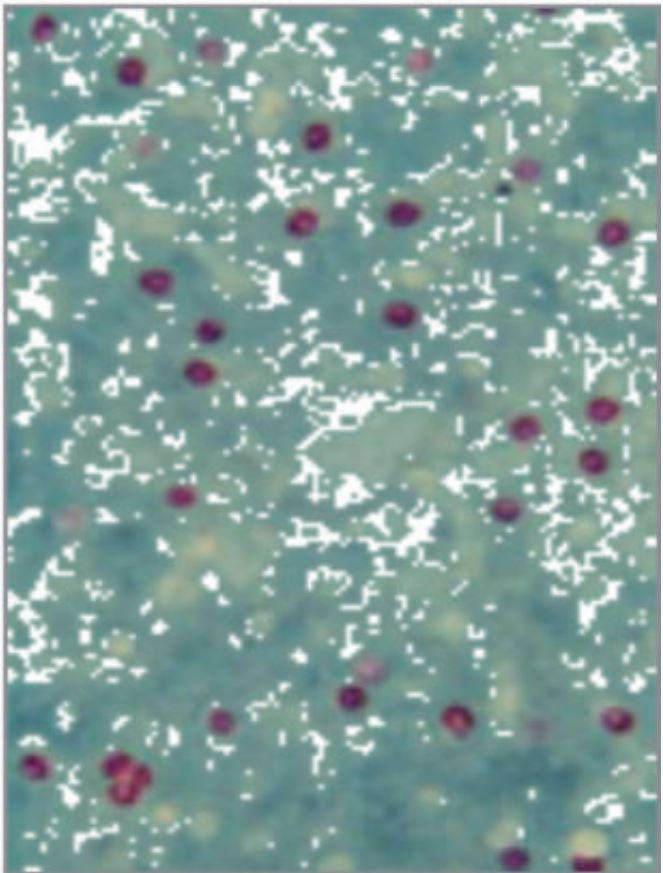

- Fig. 2. Cryptosporidium